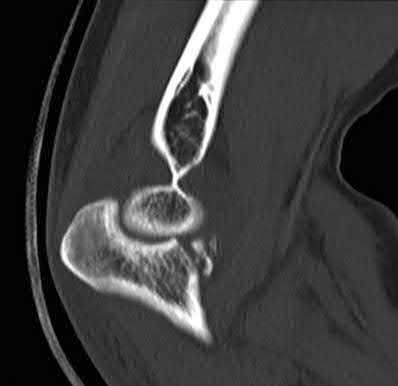

Question 3:

A 15-year-old boy presents with a permeative lytic lesion in the femoral diaphysis with aggressive periosteal reaction ('onion skinning'). Biopsy reveals uniform small round blue cells. Cytogenetic analysis of this tumor will most likely demonstrate which of the following translocations?

Correct Answer: t(11;22)

Explanation:

The clinical and radiographic description is classic for Ewing sarcoma. The characteristic cytogenetic abnormality is a balanced translocation t(11;22)(q24;q12), which fuses the EWS gene on chromosome 22 with the FLI1 gene on chromosome 11. This is seen in approximately 85-90% of Ewing sarcomas. t(9;22) is the Philadelphia chromosome (CML), t(X;18) is seen in synovial sarcoma, t(2;13) in alveolar rhabdomyosarcoma, and t(12;16) in myxoid liposarcoma.